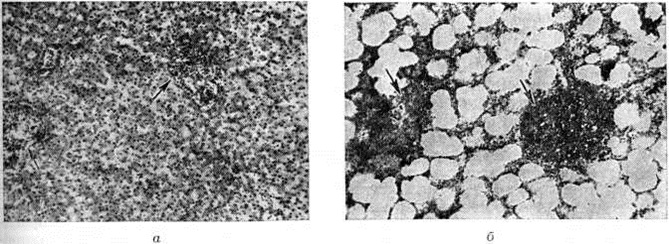

Неспецифические (параспецифические) реакции могут формироваться в нервной системе, образуя так называемый нервно-дистрофические маски, в сердечно-сосудистой системе, кроветворных органах, суставах, серозных оболочках и другие В сердечнососудистой системе и паренхиматозных органах они проявляются очаговой или диффузной гистиоцитарной и лимфоцитарной инфильтрацией (рисунок 4, а), в лимфатических, узлах — пролиферацией ретикулярных и эндотелиальных клеток, в лёгких — образованием лимфоцитарных узелков (рисунок 4, б). А. И. Струков считает, что эти реакции имеют токсикоаллергическую природу. В. И. Пузик расценивает их как результат действия микобактерий Туберкулёз в ранние периоды развития инфекционные процесса.